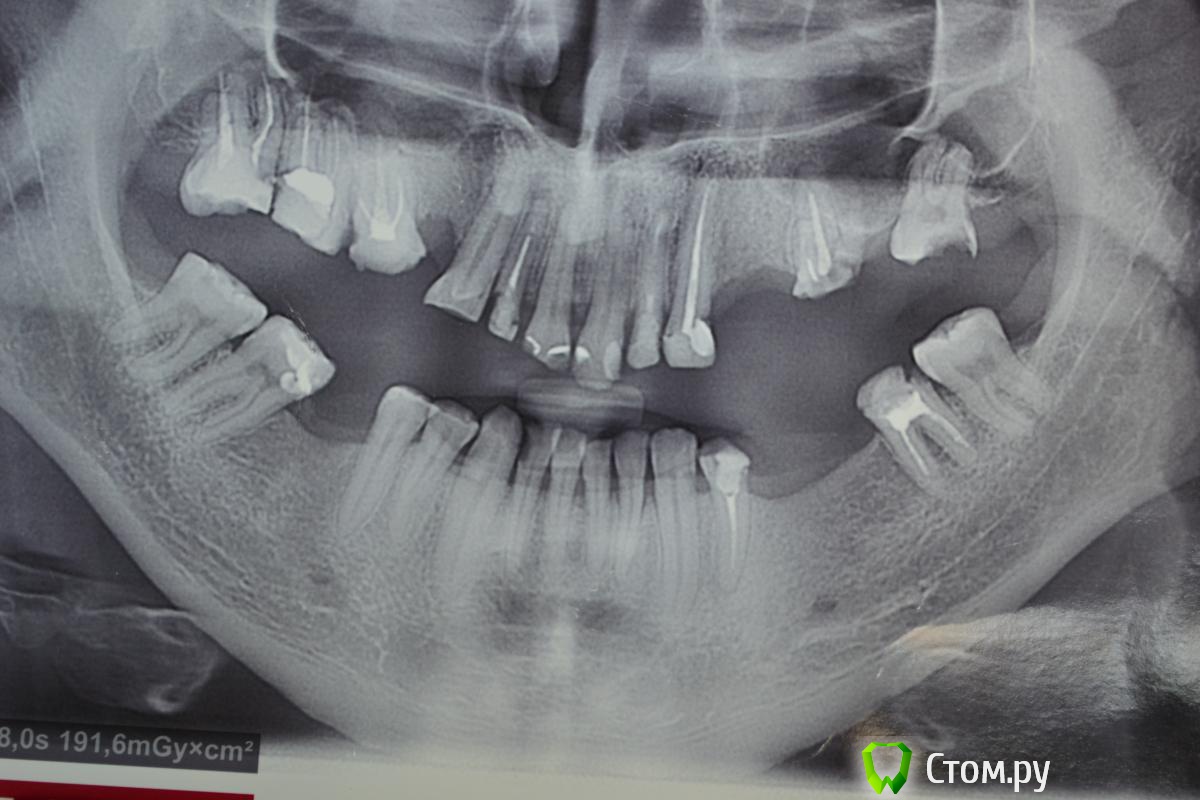

chervoncevdaniil Опубликовано 4 апреля, 2014 Поделиться Опубликовано 4 апреля, 2014 Доктора,помогите с планированием лечения у данного пациента.Краткая предистория:у пациента в июне свадьба,хочет успеть сделать себе более менее приличную улыбку.Вариант эконом,т.е. импланты,работа с мягкими тканями отпадает.На текущий момент я снял мосты,отправил на перелечивание 1.7. 2.2. и лечение кариеса 2.4 и замены пломб на 3.7. 4.7. плюс гигиена.Собственно какие бы советы я хотел услышать:1)Какие варианты протезирования на ваш взгляд здесь уместны2)Возможно ли внизу уйти от съемного протезирования3)Что делать с прикусомP.S.Прошу извинить за качество фото,фоткал первый раз и вспешке,зеркалка обычная nikon d 3100 со стандартным объективом и вспышкой,настройки установил на авто,если пару советов по дентальному фото дадите конкретно для моей камеры,буду благодарен .Модели еще не отлили,как будут,я обязательно выложу Ссылка на комментарий

chervoncevdaniil Опубликовано 11 августа, 2014 Автор Поделиться Опубликовано 11 августа, 2014 Доктора,новый пациент,проблемный для меня,фото конечно,плохие,но пока нет нормального оборудования для фотографии.Завтра приложу фото моделей.Посоветуйте,пожалуйста,что можно придумать.Бюджет ограничен суммой в 80000,при цене мк-5000,цл-3000,имплант 20000.ТО есть имплантация и ортодонтия скорее всего отпадают сразу. 1 Ссылка на комментарий

Rash163 Опубликовано 11 августа, 2014 Поделиться Опубликовано 11 августа, 2014 Доктора,новый пациент,проблемный для меня,фото конечно,плохие,но пока нет нормального оборудования для фотографии.Завтра приложу фото моделей.Посоветуйте,пожалуйста,что можно придумать.Бюджет ограничен суммой в 80000,при цене мк-5000,цл-3000,имплант 20000.ТО есть имплантация и ортодонтия скорее всего отпадают сразу.Да уж, не повезло пациенту, он свои зубы должен был береч и береч(( сам он что хочет. Есть мнение здесь далеко не 80 Ссылка на комментарий

chervoncevdaniil Опубликовано 11 августа, 2014 Автор Поделиться Опубликовано 11 августа, 2014 Да уж, не повезло пациенту, он свои зубы должен был береч и береч(( сам он что хочет. Есть мнение здесь далеко не 80Ну прям уж Голливуд ему не надо,но более менее в приличный вид привести все хочет.Я просто не понимаю что с таким прикусом делать ичто можно с ним сделать только ортопедически Ссылка на комментарий

doktor vv Опубликовано 11 августа, 2014 Поделиться Опубликовано 11 августа, 2014 Даниил,портретную съемку делаете?(профиль,анфас)Здесь 3ий класс-было бы неплохо сделать ТРГВ идеале в данном кейсе без ортохирургии ничего не сделатьПри бюджете в 80 рублей работать придется в существующей окклюзииЖдем моделей Ссылка на комментарий

chervoncevdaniil Опубликовано 11 августа, 2014 Автор Поделиться Опубликовано 11 августа, 2014 Даниил,портретную съемку делаете?(профиль,анфас)Здесь 3ий класс-было бы неплохо сделать ТРГВ идеале в данном кейсе без ортохирургии ничего не сделатьПри бюджете в 80 рублей работать придется в существующей окклюзииЖдем моделейМогу в пятницу сделать,у меня у фотоаппарата вспышка сломалась,поэтому снимаю,как в ночи.То что тут третий класс,это понятно.ТРГ в нашем городе сложно,могу отправить в Ярославль,но сомневаюсь,что пациент настолько мотивирован,да и соглашусь я с вами,при том бюджете,который озвучил пациент, работать придется в привычной окклюзии Ссылка на комментарий